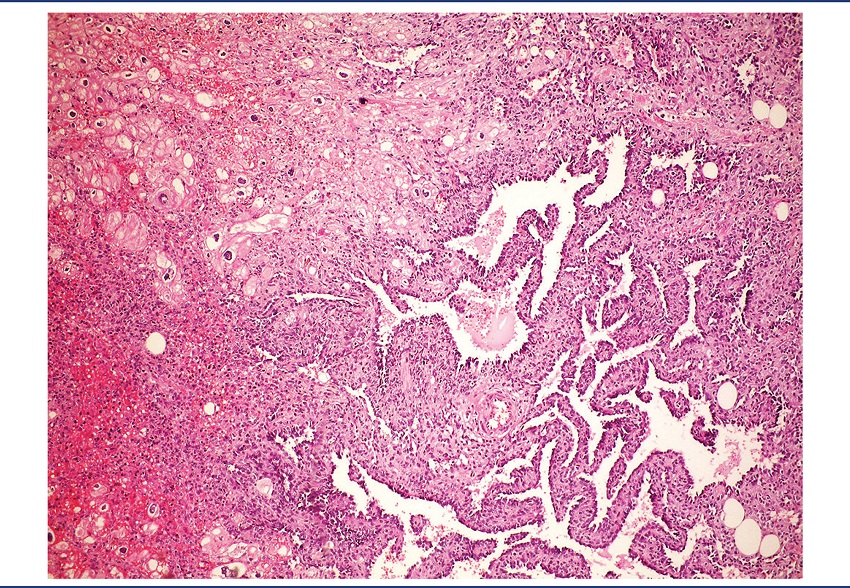

On pathological examination, the specimen was received fragmented, measuring 9.2 × 7 × 4 cm. There was a brownish nodule with hemorrhagic areas, measuring 4 cm in diameter, apparently infiltrating the cardiac wall (Figure 2). Microscopically, it was identified as a mesenchymal neoplasm, characterized by the proliferation of atypical endothelial cells with irregular nuclei, sometimes round sometimes spindle, without evident nucleolus, forming vascular spaces, papillae, and solid areas. Mitoses were frequent and necrosis was not observed. The lesion permeated cardiomyocytes, which presented clear cytoplasm and hypertrophic nucleus (Figures 3 to 7). There was infiltration of the visceral pericardium. The diagnosis was primary cardiac angiosarcoma.

HE: hematoxylin and eosin.

Grossly, angiosarcomas are large multilobulated dark brown or black tumors, measuring 2-10 cm. The tumor mass permeates the myocardium and can fill the atrial cavity. The pericardium is generally infiltrated, and in rare cases can be the primary site of the neoplasm(7,9).